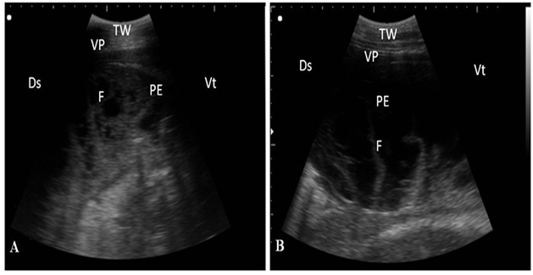

Ultrasonography of pleurisy in cows using a 3.5 MHz transducer. (A) The image shows the presence of thick fragmented visceral pleura and pleural sac filled with echogenic fibrin shreds and anechoic exudates. (B) The image shows pleural effusion and echogenic fibrin shreds. Visceral pleura (VP), fibrin (F), pleural effusion (PE), and the thoracic wall (TW). The right part of the image is ventral (Vt) and the left is dorsal (Ds).